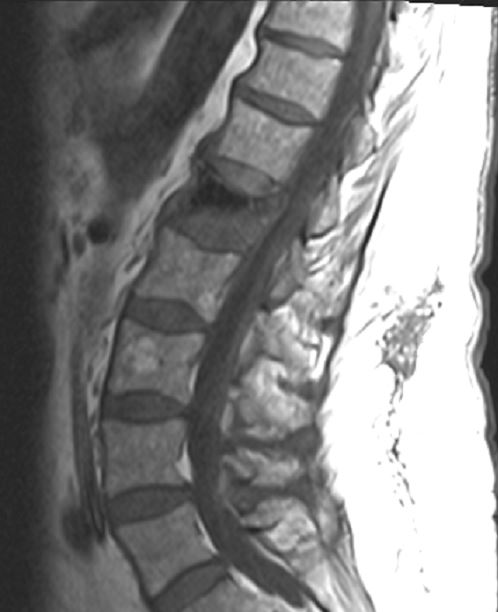

On May 17, 2016, I somehow managed to completely crush my L1 vertebra, by sustaining what is called a “burst fracture”. A wonderful procedure called a kyphoplasty was recommended and scheduled. While I was in a Skilled Nursing Facility waiting for the kyphoplasty, I also managed to add stenosis at the L1 vertebra. I moved just right, and “pop”, there it went. Stenosis is a narrowing of the space occupied by the spinal cord. In my case, it is caused by a shift in the placement of the L1 vertebra. The nerves that leave the spinal cord at this location affect the pelvic floor and upper legs. The kyphoplasty was performed on June 22, 2016, and went very well. The stenosis, however, is still causing a lot of discomfort, and is preventing me from being truly functional. A very competent spine surgeon is analyzing the injury, to determine the best treatment plan. The surgeon and I are both hoping to avoid more surgery, as this would be “serious” spine surgery – the kind that puts the patient at risk for paralysis, and can involve removing ribs or lungs to access the spine.

"Lumbardini", the L1 vertebra that disappeared just like Houdini.

"Lumbardini", the L1 vertebra that disappeared just like Houdini.